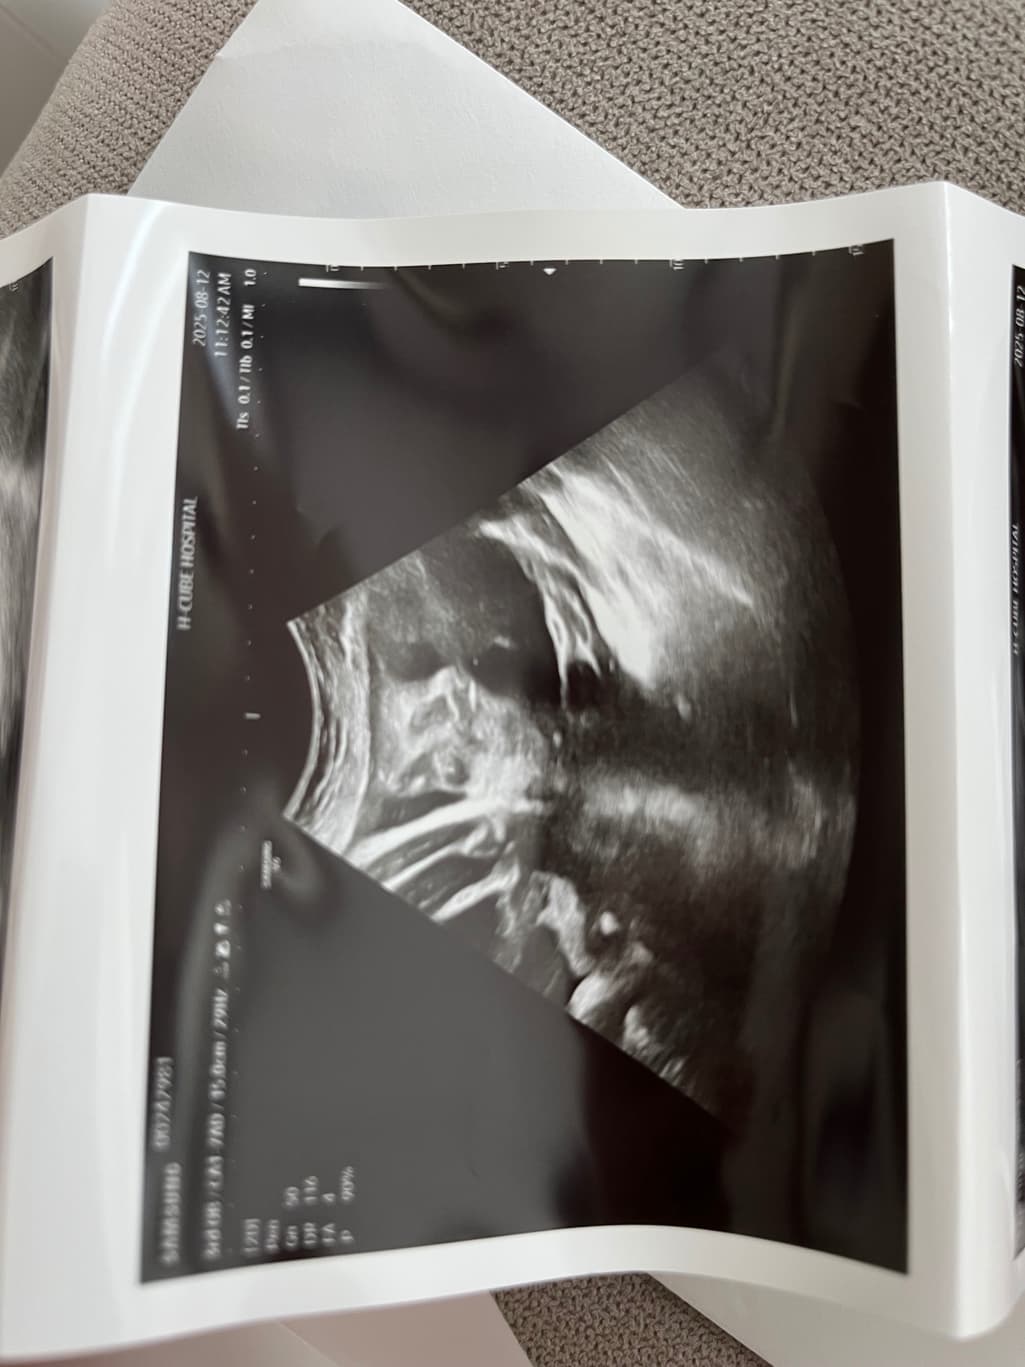

안녕하세요, 사진 순으로 24주차 입체초음파, 그 다음 두 장은 36주차 일반 초음파 사진입니다.

다름이 아니라 36주차 사진상 아이 눈 간격이 너무나 좁아보여서 걱정이 되어서 여쭈어봅니다..

옆으로 눌린 자세라 일시적으로 그렇게 보일 수 있는건지, 아니면 실제 저렇게 눈 간격이 좁은 아이의 경우도 있는지 궁금합니다.

초음파는 3차원의 물체를 2차원적 영상으로 표현하지요. 공간상 왜곡으로 보이며, 사실 특별한 소견으로 생각되지 않아요.

다운증후군일 경우에도 눈이 좁아보이거나 할 수 있지만, 이는 초음파로 눈의 간격을 확인하는 것이 아닌 목덜미 투명대, 심장구조 등을 보면서 평가하는 것이지, 질문자분이 걱정하시는 바가 아닙니다. 그리고 관련해서 문제가 있었다면 진즉에 담당 주치의가 설명을 했을 부분입니다.